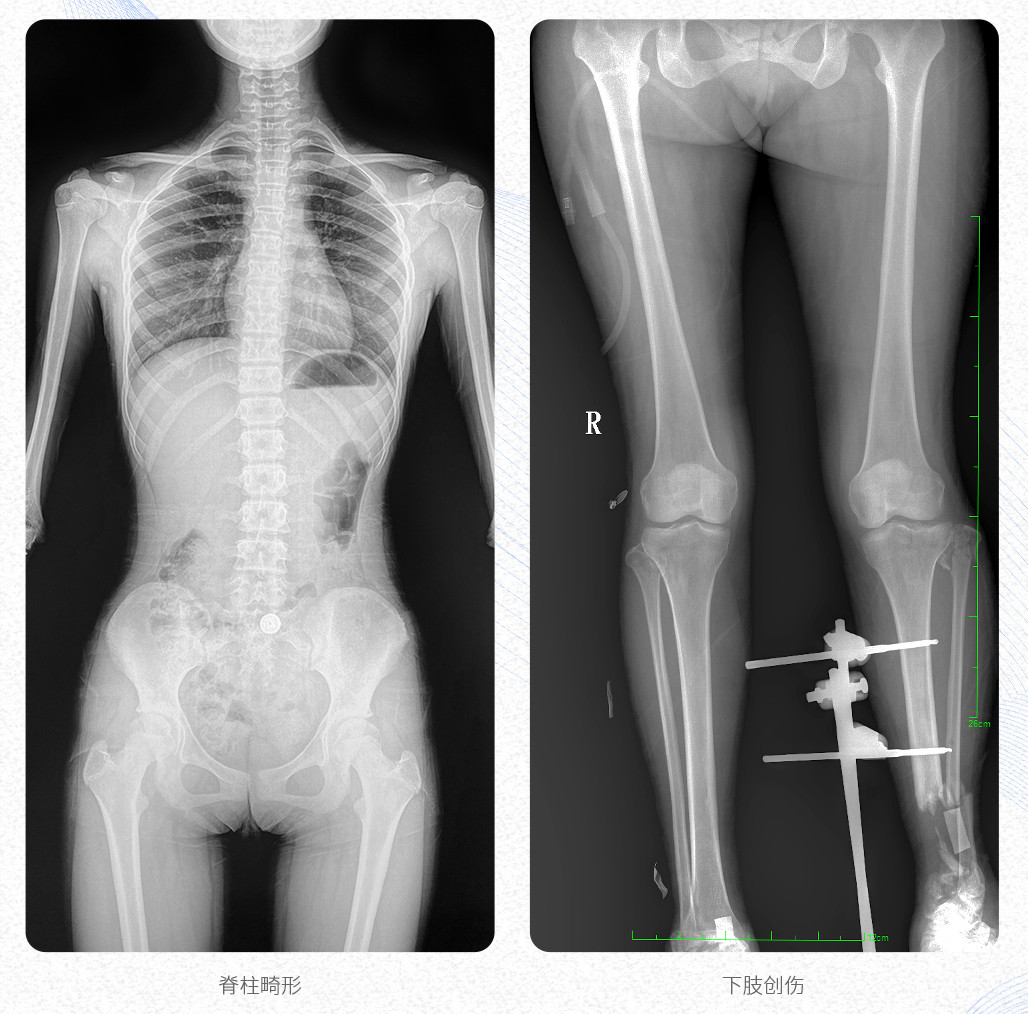

應(yīng)用科室:骨科、創(chuàng)傷科、脊柱正畸科、放射介入科等。

臨床應(yīng)用:支持全脊柱攝影、雙下肢攝影、脊髓造影、復(fù)雜創(chuàng)傷、人工關(guān)節(jié)置換、關(guān)節(jié)損傷的修復(fù)重建等大視野臨床應(yīng)用。

17"*34"有效視野,是市面大尺寸平板的2倍,一次成像不拼接。相較于多張攝影再軟件拼接的DR設(shè)備,PLX8600解決了拼接圖像存在密度不均勻,拼接處圖像配準(zhǔn)和放大效應(yīng)等問(wèn)題,給臨床帶來(lái)了真正的大視野影像解決方案,高清畫質(zhì),準(zhǔn)確成像不失真,可一次性覆蓋全脊柱或雙下肢影像。PLX8600大視野平板動(dòng)態(tài)DR攝影速度快,患者可以更快的完成檢查,且單次攝影輻射劑量是常規(guī)多張攝影再軟件拼接DR的1/2或1/3,低劑量給患者更多關(guān)愛(ài)。

PLX8600大視野平板動(dòng)態(tài)DR可在低輻射劑量下獲得患者站立位、臥位的高質(zhì)量影像。搭載自主研發(fā)的圖像均衡處理系統(tǒng),能夠很好的均衡人體不同厚度組織的影像,視野大,圖像清晰,層次豐富。